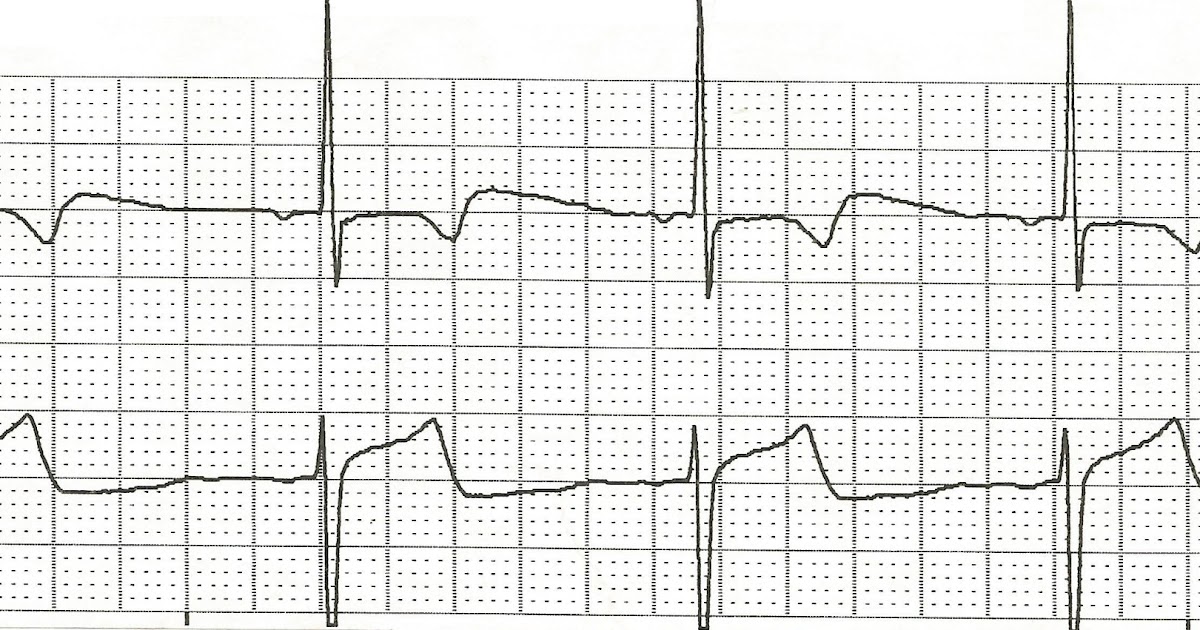

Inferior Wall M.I. With Junctional Rhythm ECG Guru Instructor Resources

From ecgguru.com

Inferior Wall M.I. With Junctional Rhythm ECG Guru Instructor Resources Is Junctional Rhythm Irregular A junctional rhythm happens when an abnormal heart rhythm comes from the av node or his bundle. Junctional rhythm also called nodal rhythm[2] describes an abnormal heart rhythm resulting from impulses coming from a locus of tissue in. A junctional rhythm is an abnormal heart rhythm that originates from the av node or his bundle. Although the heart has other. Is Junctional Rhythm Irregular.